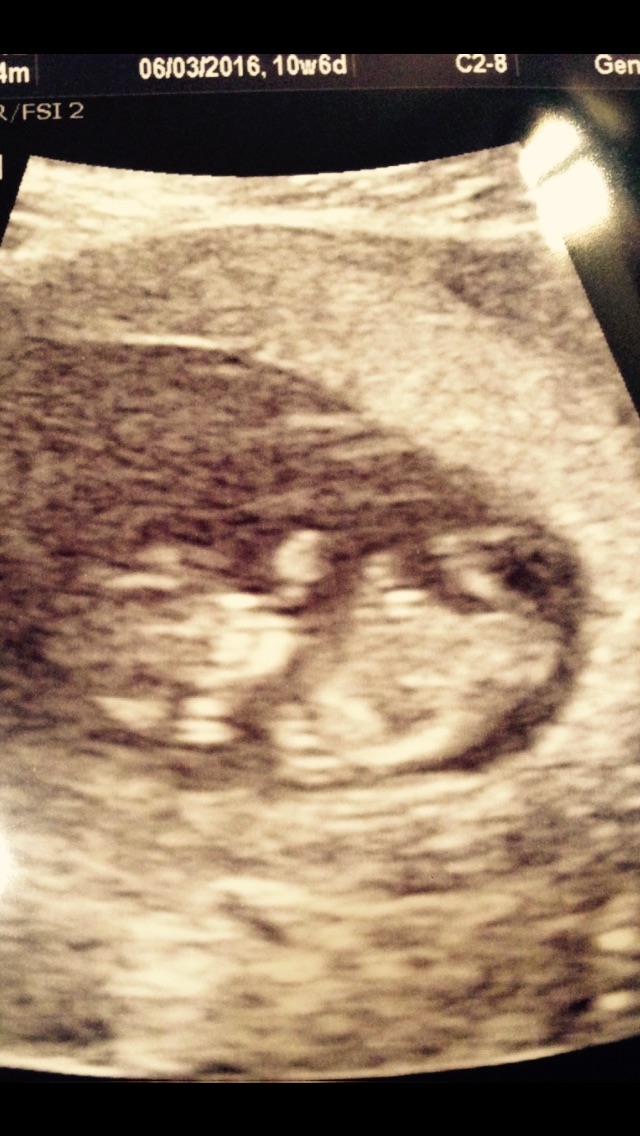

Here is our sweet little babe as of Friday! (10 w 4 d)

image.jpg